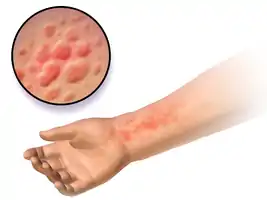

| Hives on the upper leg, note how they are slightly raised | |

| Symptoms | Red, raised, itchy bumps[2] |

Hives, also known as wheals and urticaria, is a kind of skin rash with red, raised, itchy bumps.[1][2] They may also burn or sting.[3] Often the patches of rash move around.[3] Typically they last a few days and do not leave any long-lasting skin changes.[3] Fewer than 5% of cases last for more than six weeks.[3] The condition frequently recurs.[3]

Hives, or urticaria, is a form of skin rash with red, raised, itchy bumps.[2] They may also burn or sting.[3] Welts (raised areas surrounded by a red base) from hives can appear anywhere on the surface of the skin. Whether the trigger is allergic or not, a complex release of inflammatory mediators, including histamine from cutaneous mast cells, results in fluid leakage from superficial blood vessels. Welts may be pinpoint in size or several inches in diameter. Often the patches of rash move around.[3]

Hives on the left chest wall. Notice that they are slightly raised.